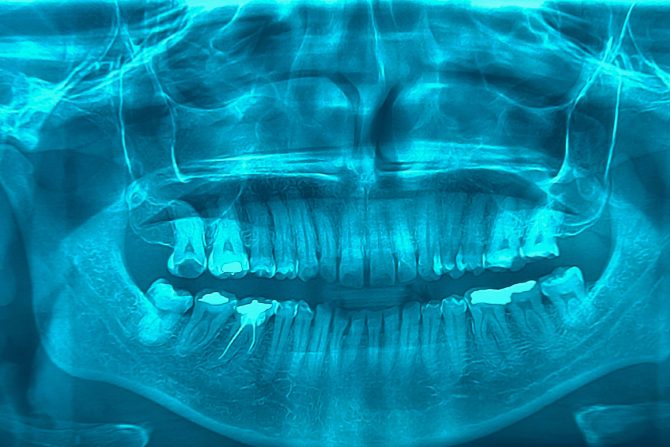

- Zubar će savetovati rendgensko snimanje zuba i vilice, pregledati zube -  objašnjava dr Alšerbini. U slučaju da bol nije posledica karijesa ili upale desni možda će biti potrebno da posetimo neurologa ili ORL specijalistu. Nekada se savetuju dodatna ispitivanja, snimanje magnetnom rezonancom ili skeniranja sinusa, da bi  se utvrdilo da li je bol posledica problema sa sinusima ili nervima.